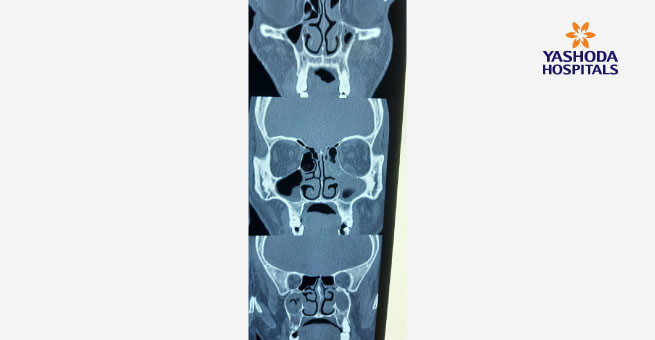

Mucormycosis: Black Fungus Disease Post Covid-19 Alert

An Increased surge of Mucormycosis disease also known as ‘Black Fungus’ has been found in patients with COVID-19. The disease starts from the nose and sinus, then quickly spreads to the eyes and the brain. On an average, 50 percent of patients may not even survive despite being provided with the best treatment possible, if the fungus spreads to the brain and then there is hardly any chance for the patient to survive. It used to be a rare disease, doctors attended to hardly one case a year, but now the circumstances have changed and ENT specialists are seeing an increased incidence of mucormycosis in patients with active COVID-19 or who have recovered from it . Most of the patients with Mucormycosis are diabetics and have a history of taking steroids for Covid treatment that raises their sugar levels.

The key for this treatment is to have a high index of suspicion and timely intervention. Immediate surgery is required to remove the affected dead tissue and bone from the nose, mouth and some patients require removal of their eyes also. After that / Concurrently the patient needs Antifungal injection Amphotericin B which has to be taken for 4- 6 weeks to avoid any further spread of disease.